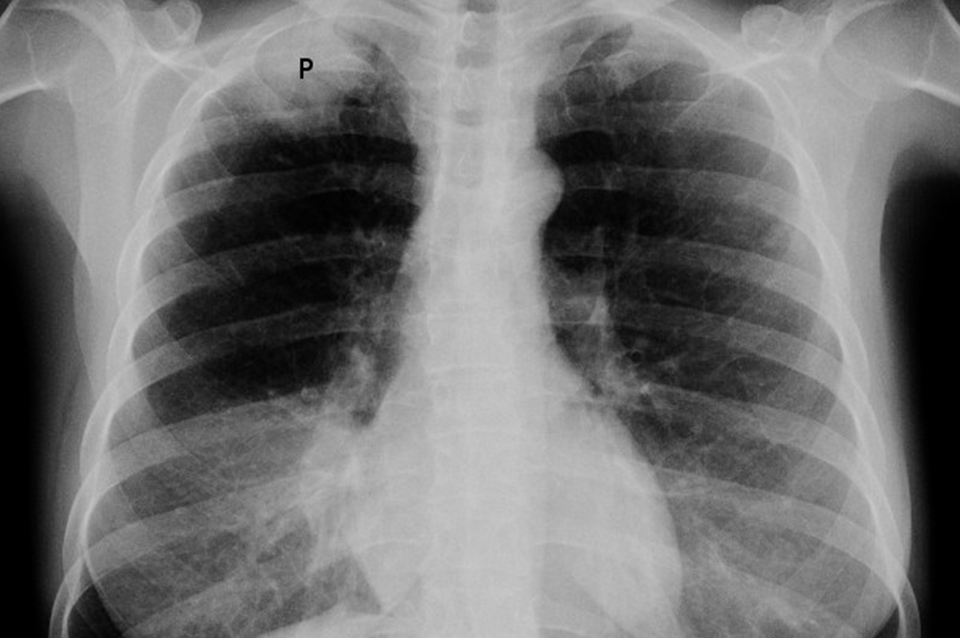

Al día siguiente, una nueva radiografía demostró que el pulmón izquierdo del chico se había “desinflado” y había vuelto a la normalidad.